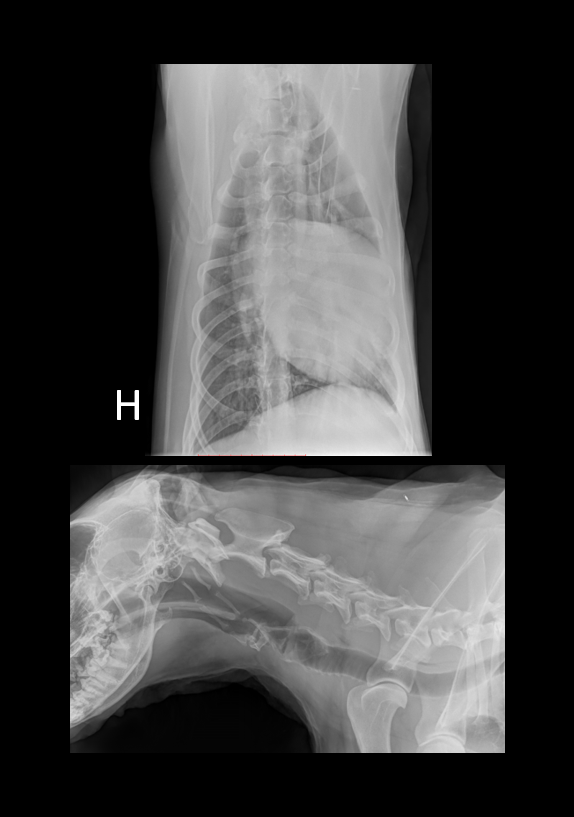

Denne gangen har vi lyst til å dele et kasus som vi syns er ganske interessant. Studien ble sendt inn til oss fra Dyrlegene i Skolestua, og sammen kom vi frem til en diagnose som kan forklare hundens problemer. Signalement: Pyreneerhund, tispe, 9år Anamnese: Eier syns hunden har blitt i dårligere form over tid, den bruker lang tid på å spise, tiltagende hosting. Eier har sau, så hunden jobber som vokterhund. Etter anstrengelse bruker hunden lang tid på restitusjon, peser lenge.